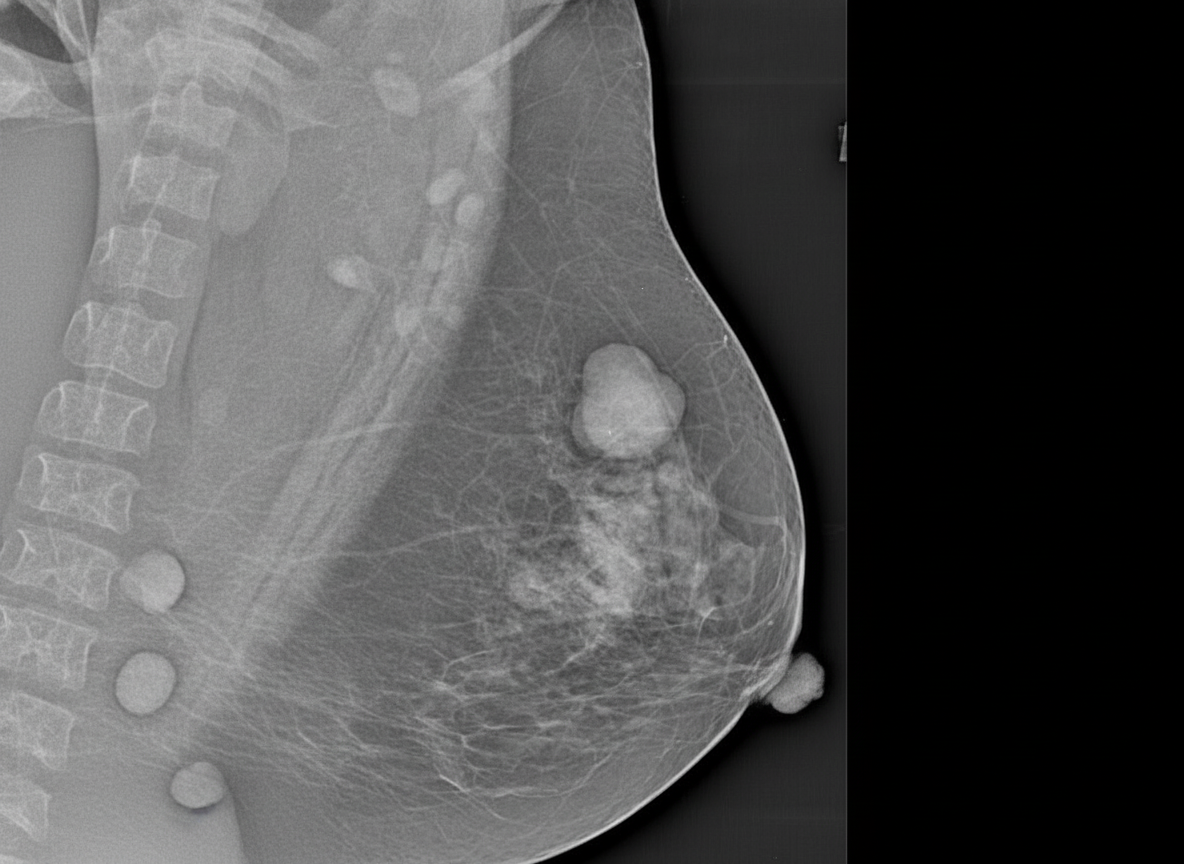

An MLO view of the left breast is shown. What is the MOST likely diagnosis?

Explanation: ***Fibroadenomas*** - Appear as **well-circumscribed**, **oval** or **lobulated masses** with smooth margins on mammography, often containing **coarse calcifications**. - Typically present as **mobile**, **painless lumps** in young women and may show **involuting calcifications** in older patients. *Papillomatosis* - Mammographically presents with **microcalcifications** in a **ductal distribution** rather than well-defined masses. - Associated with **nipple discharge** and appears as **branching microcalcifications** following ductal anatomy. *Fat necrosis* - Shows characteristic **rim calcifications** or **eggshell calcifications** around **lucent centers** representing necrotic fat. - Often has a history of **trauma** or **surgery** and appears as **irregular masses** with **spiculated margins** initially. *Oil cysts* - Appear as **round**, **lucent lesions** with **thin walls** and **rim calcifications** on mammography. - Represent **chronic fat necrosis** and show **fluid-fluid levels** or **fat-fluid levels** on imaging.